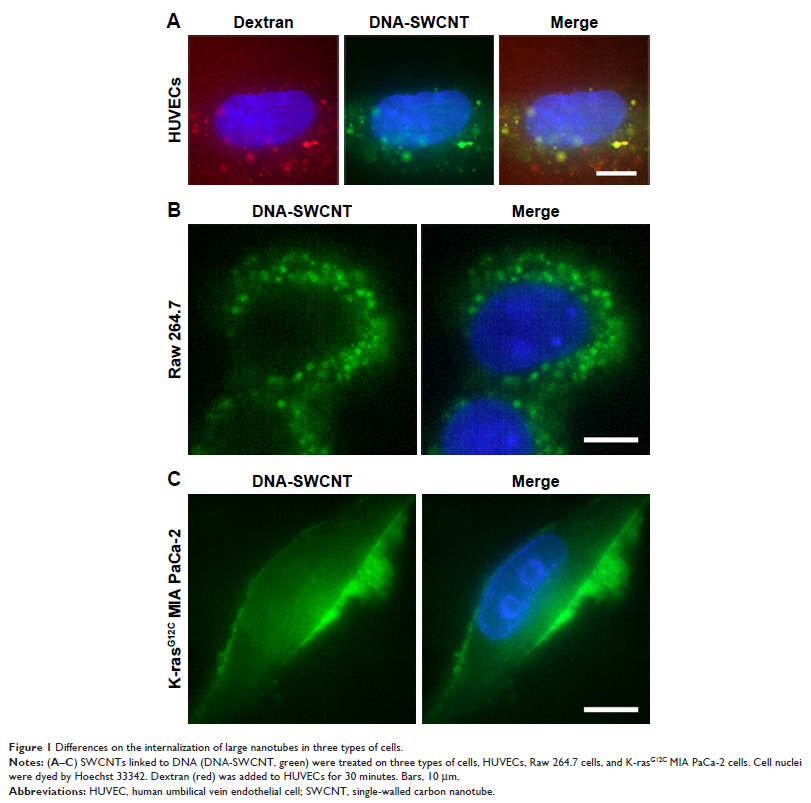

Original Research 视频

通过 3D-SIM 高分辨率显微镜探索细胞的巨胞饮内化结构尺寸及特征

- 作者:Jing Jin, Yanting Shen, Biao Zhang, Rong Deng, Dianshuai Huang, Tianqi Lu, Fei Sun, Shuping Xu, Chongyang Liang

- 期刊:International Journal of Nanomedicine